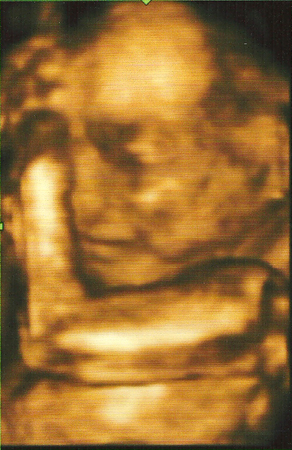

oksana 15 лет а вот и мы. нам уже 21 неделя. мальчик. рост19. 58 см вес 536г. Посмотрите еще 20 записей на эту тему Отменить Ответить Oksana(отдых на Сицилии) Какое 4удо!!!!!! Маленький такой, хорошенький)))) как заме4ательно когда внутри живет маленький 4елове4ик) 19.09.2010 Ответить Katerina Прелесть!!!!ПУСТЬ РАСТЕТ ЗДОРОВЕНЬКИМ!!!!!!!!! 19.09.2010 Ответить oksana срасибо. 19.09.2010 Ответить ну вот была на очередной раз у гинеколога. Чаты Беременных Выберите чат: Январята-2026 Февралята-2026 Мартята-2026 Апрелята-2026 Майчата-2026 Июнята-2026 Июлята-2026 Августята-2026